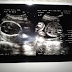

Foto USG Dede' (2)

Foto USG Dede', 27 Januari 2014. Minggu ke-20, she's a GIRL.